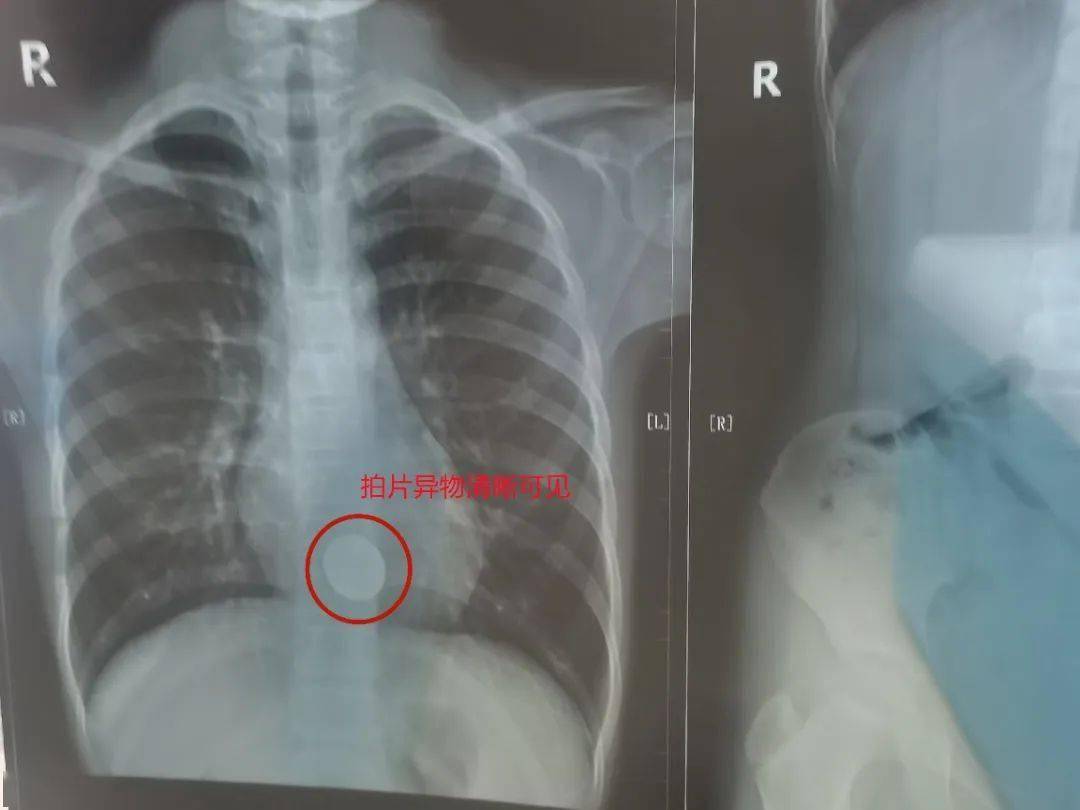

» 吞 下 一元 硬币 (99) 사진

吞 下 一元 硬币 (99) 사진

一元 硬币